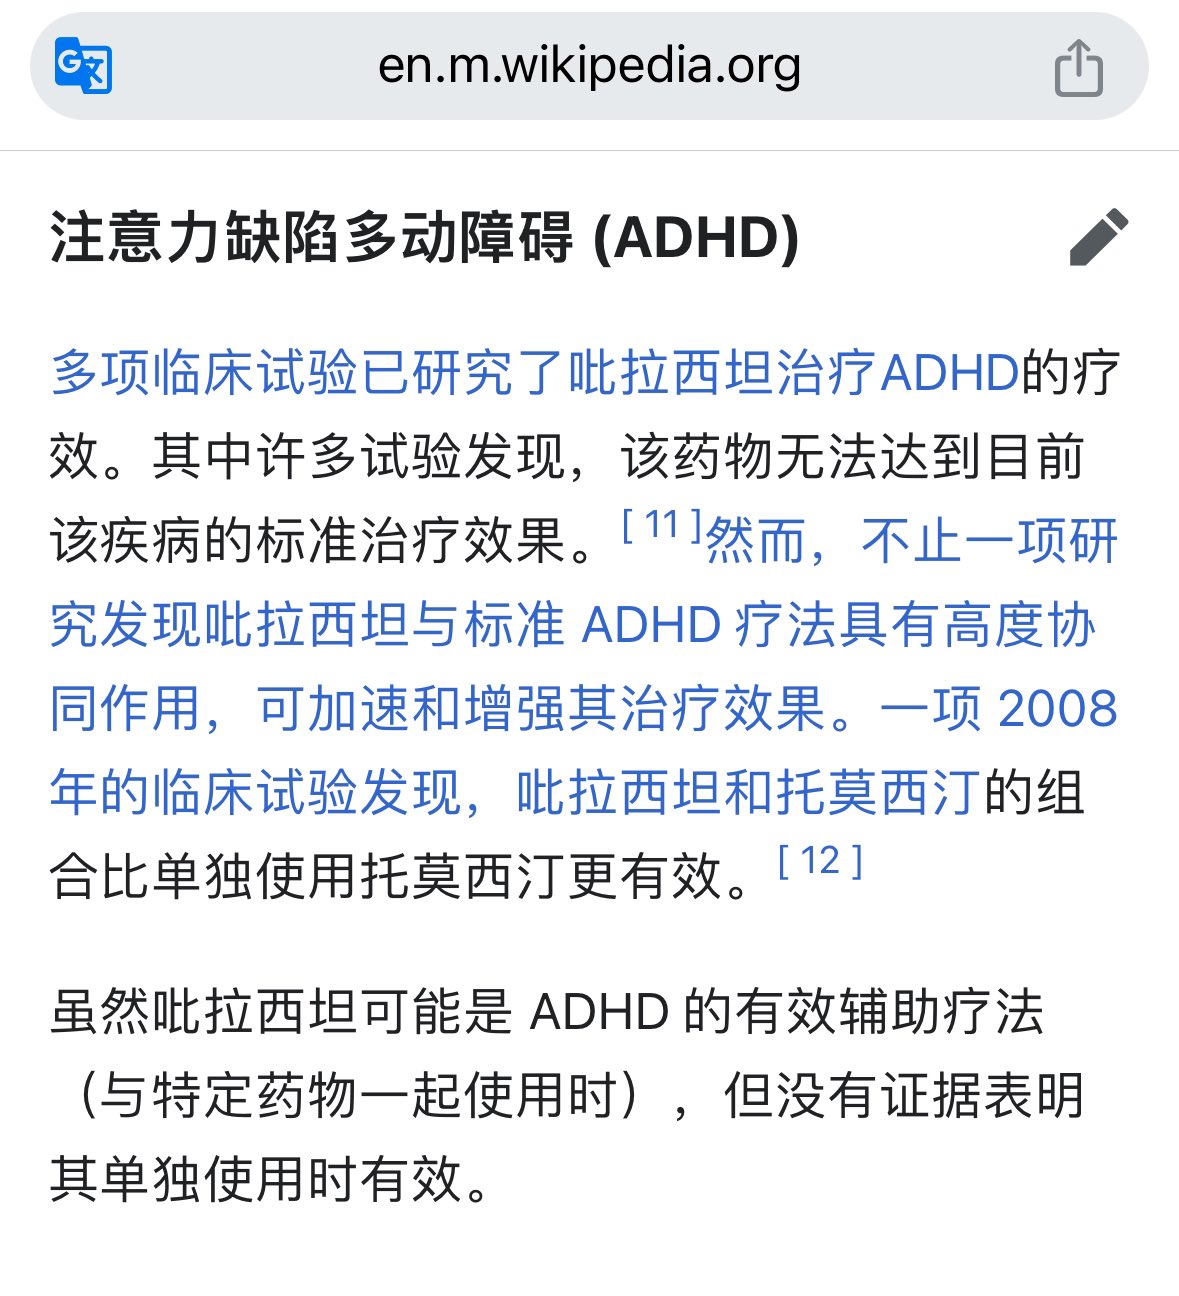

首先,从定义上讲,“反解离(anti-dissociative)”并不是一个标准的医学术语或者广泛认同的药理学分类。在正规资料,比如医学文献、维基百科、精神药理学教科书中,目前并没有“反解离药物”这个正式概念。

看上去像是为了描述某类特定效应而创造的术语(可能是nmda受体活性增强),用来对抗因NMDA受体拮抗剂(比如氯胺酮、DXM、PCP等)引发的解离体验(dissociation)。

那么更常见的是将其归入认知增强剂(cognitive enhancers),特别是改善认知连接性(connectivity)和现实感知(reality testing)的类型。

但其实在药理学上,单纯用“受体激动剂”来逆转“受体拮抗剂”的效应,有时会导致过度激活。

对于NMDA受体而言,过强的NMDA活化本身就与兴奋性毒性(excitotoxicity)和精神病样症状(psychotomimetic effects)有关,比如谷氨酸风暴可以引发严重的焦虑、妄想、乃至癫痫。

也就是说,简单地“激动-解除拮抗”在中枢神经系统是很危险的做法,尤其是对于易感个体(如有精神分裂素质的人)。

科学的处理方式一般是通过更细致的调节,比如微调NMDA/AMPA平衡、调节其他辅助途径(如GABA、5-HT、mGluR受体),而不是简单粗暴地用“NMDA增强剂”去顶回去。

而临床处理药物中毒中,其实医生更常用的做法是保守、支持性的治疗,比如补液,促进代谢,必要时镇静,以及监测生命体征防治并发症。

药物拮抗与受体激动之间,往往牵扯到的是复杂的适应性变化(receptor upregulation/downregulation),

不是简单的“给多一点刺激就能抵消”的关系